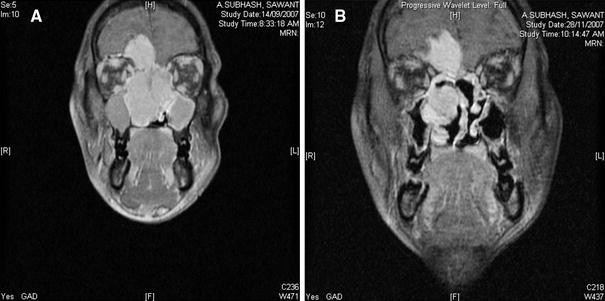

A 23-year old Indian male presented to Tata Memorial Hospital with a 3-month history of nasal stuffiness, nasal bleeding, nasal twang in voice, anosmia and increasing headache. His medical and social history was unremarkable. On examination, he had fullness of the cheek and nose on the left side. Lymphnodes, thyroid and salivary glands were non-palpable. Tumour markers (serum alfa-feto protein and beta-human chorionic gonadotropin) were within normal limits. Radiographs and computerized–tomography scans showed a large bone destroying and heterogeneously enhancing lobulated mass involving the left nasal cavity, maxillary, ethmoid and frontal sinuses, right nasal cavity with intracranial and retrobulbar extension (Fig. 1a). His blood counts and biochemical investigations were within normal limits.

Fig. 1

a A large enhancing mass in the nasoethmoidal region with erosion of cribriform plate and large intracranial extension in the anterior cranial fossa. (pre-chemotherapy MRI). b Decrease in the size of the mass as compared to the prechemotherapy MRI (Post-chemotherapy MRI)

A course of neoadjuvant chemotherapy comprising four cycles of cisplastin and adriamycin was administered to the patient. The post-chemotherapy MRI scan revealed a partial response in the extracranial portion, with no response in the intracranial part (Fig. 1b). Subsequently, an endoscopic-assisted craniofacial resection was performed on the patient for a T3N0 sinonasal tumour.